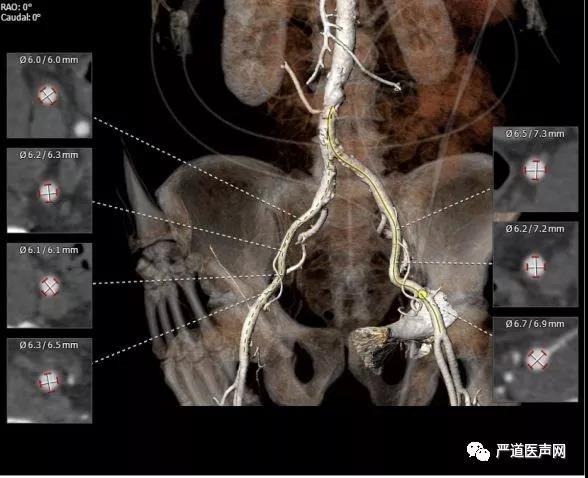

术前CT:

瓣环直径28.4 mm * 19.4 mm(平均径23.9mm)

周长76.8mm

面积444.7 mm2

乏氏窦直径26.5 mm * 33.4mm (平均径30.0 mm)

左冠开口高度14.9mm

右冠开口高度 15.3mm

瓣膜中度钙化

横位心:成角57度

选择左侧股动脉入路